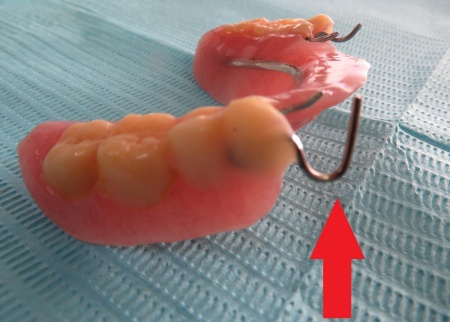

80代女性 部分入れ歯の金属バネを修理して再び使えるようにした症例

- 部分入れ歯

- 治療期間の目安 -

- 治療回数の目安 1回

-

治療費総額の目安

約1,000円

(保険診療1割負担)

治療のリスク

・着脱式のため、食後の清掃が必要です ・最初のうちは異物感があり、慣れるまで時間がかかる場合があります ・慣れるまでは、入れ歯の裏側の粘膜に傷ができる場合があります...

by.いとう歯科医院

2026/03/30